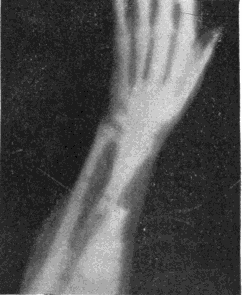

Fig. 1.—Head.

Fig. 2.—Broken Arm, Overlapping.

(Due to defective setting.)

Fig. 3.—Ribs.

Fig. 4.—Knee, Knickerbocker Buttons, Bullet in Femur.

FROM SCIAGRAPHS BY PROF. DAYTON C. MILLER. § 204.